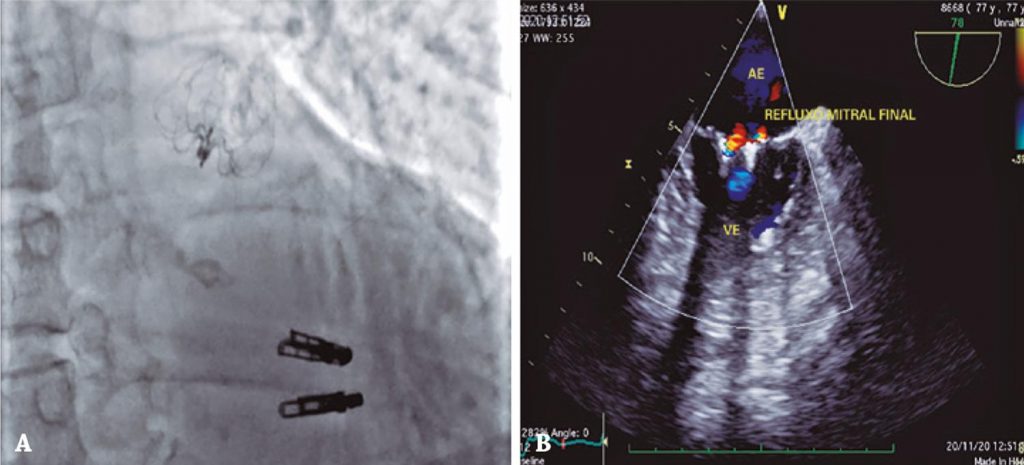

Combined MitraClip® implantation and left atrial appendage occlusion using the Watchman™ device

We describe here a combined implantation using the MitraClip® system and the Watchman™ device for the treatment of primary MR and LAA occlusion. A 77-year-old female patient with history of breast cancer treated with surgery and radiation therapy, previous thromboembolism, permanent atrial fibrillation treated with oral anticoagulant (OAC) (edoxaban), presented with an important MR due to myxomatous degeneration and angiodysplasia of the colon, with several episodes of intestinal bleeding.